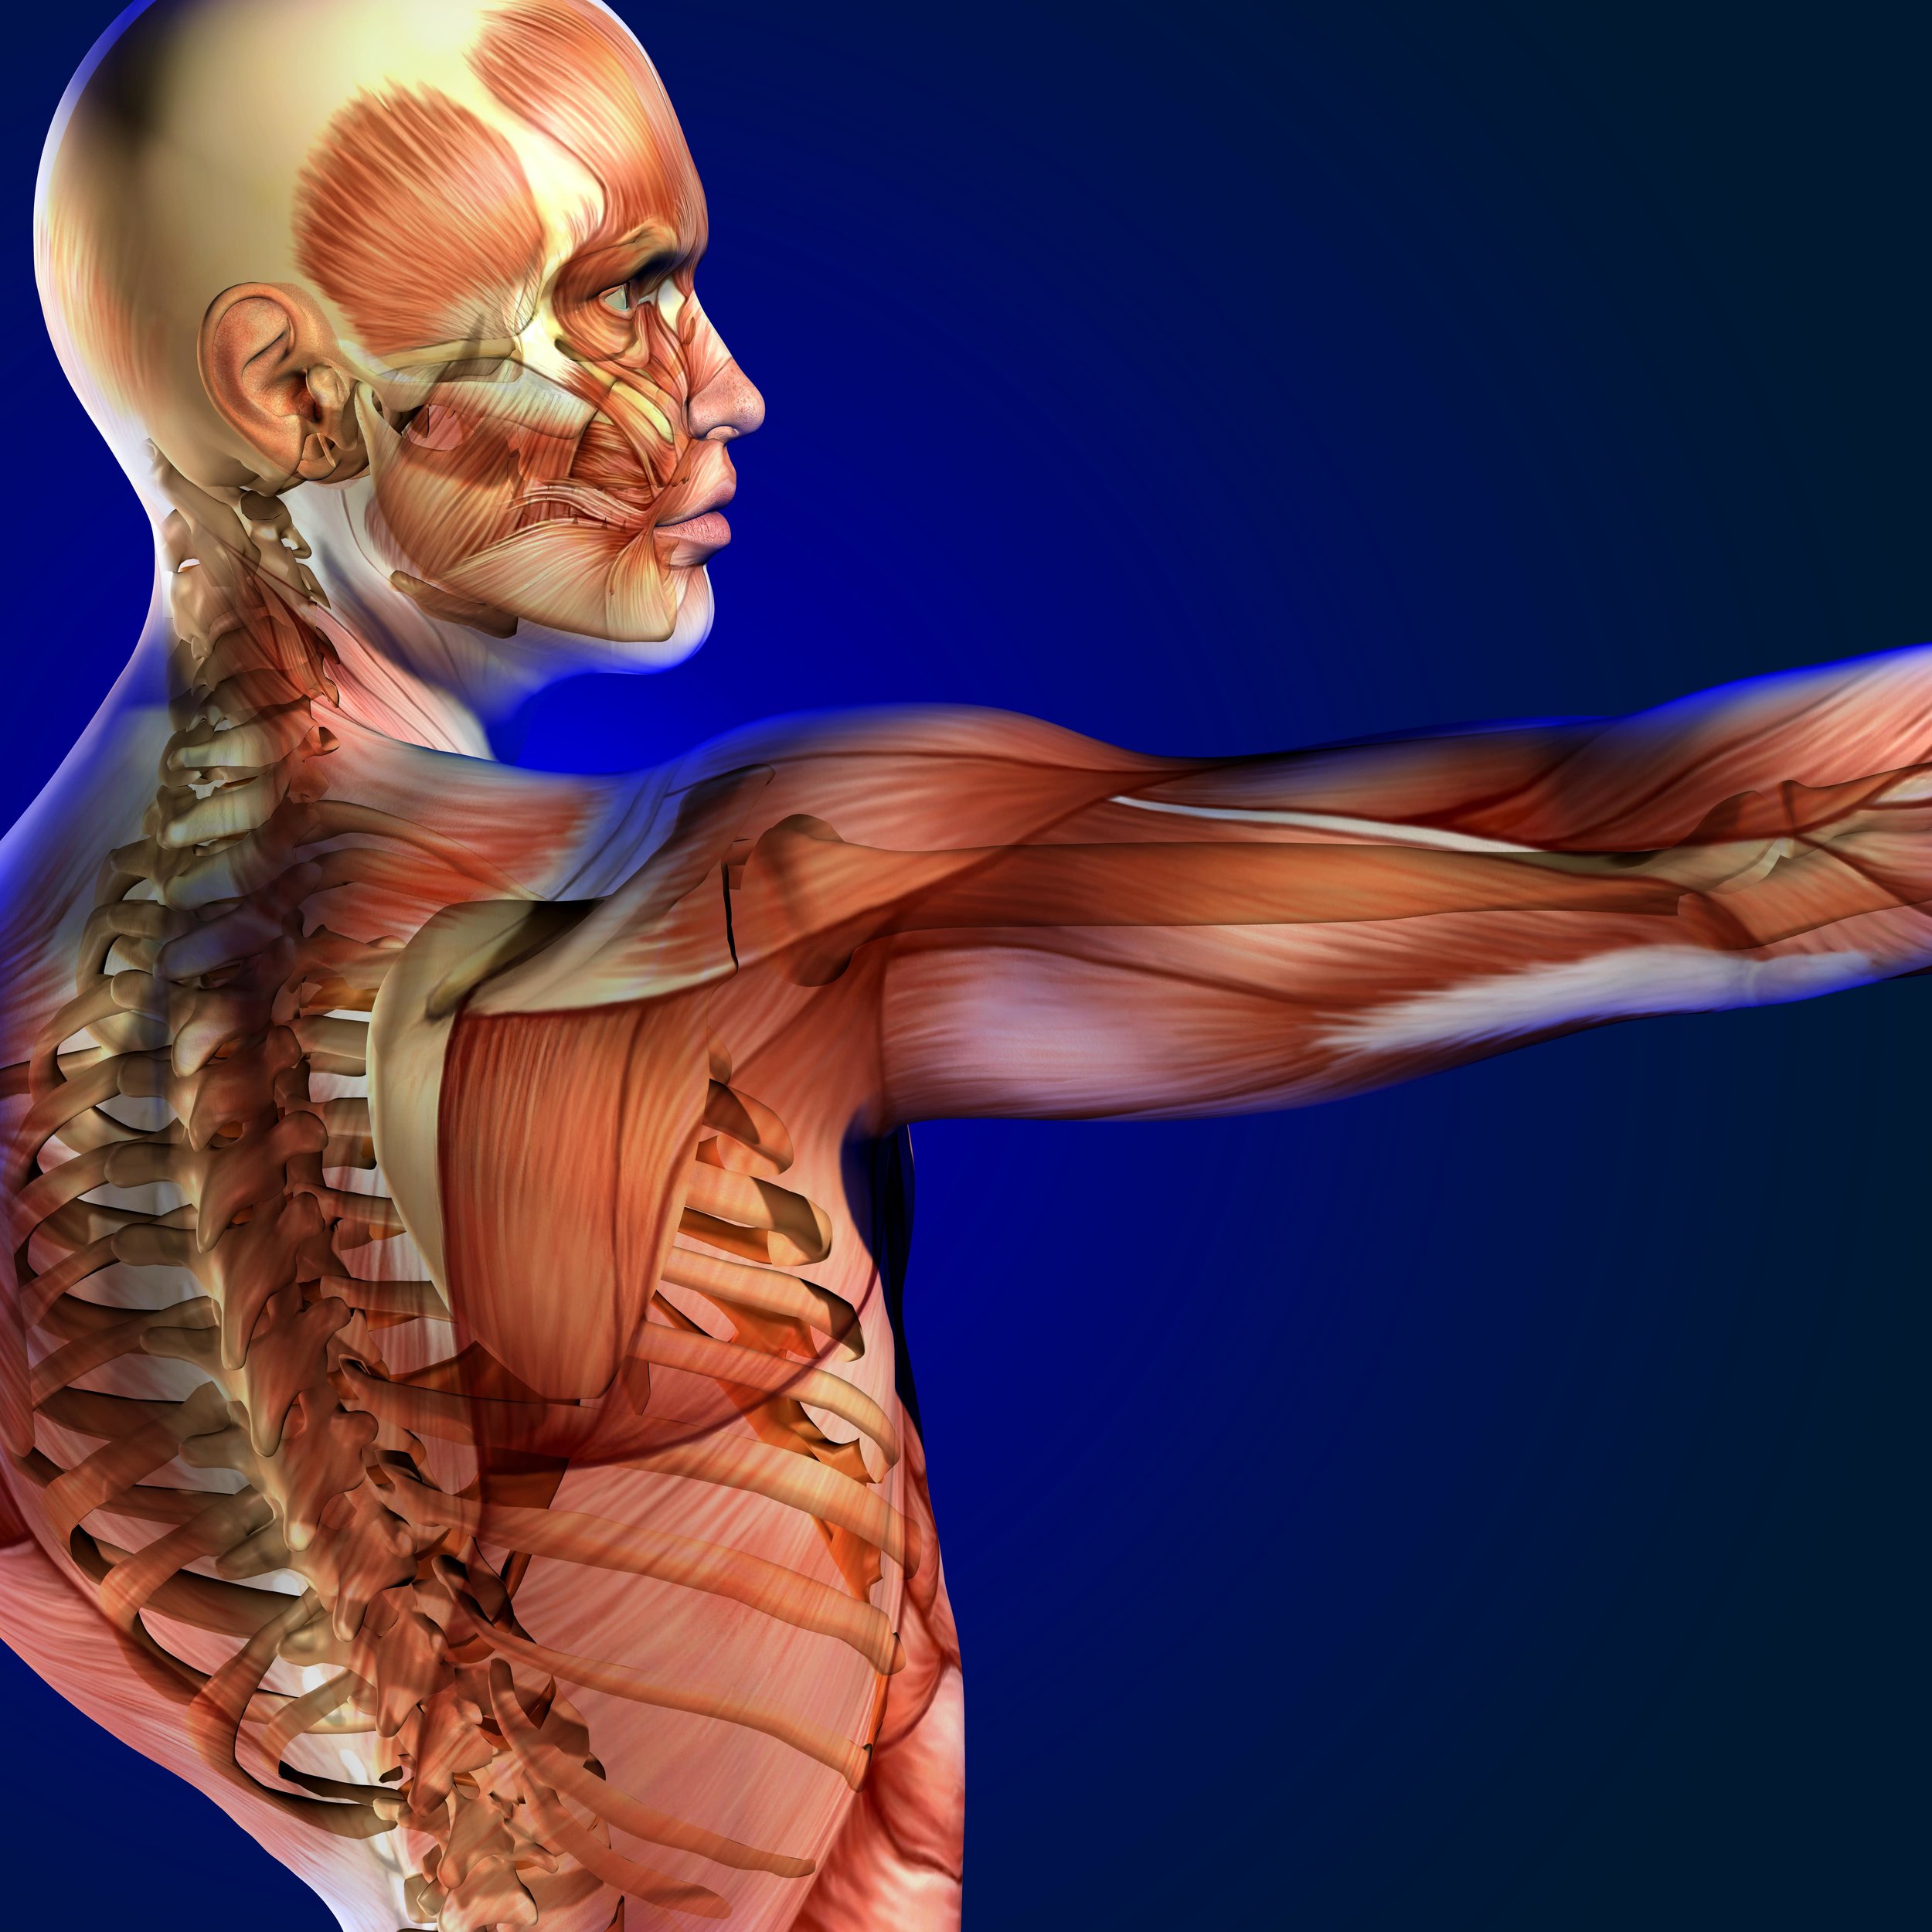

Patients seek chiropractic care for lower back pain, sciatica, neck pain, headaches, athletic related issues, pinched nerves, muscle spasms, knee and joint pain, muscle spasms, rotator cuff injuries, rib pain or breathing difficulties. Chiropractors focus on the effects that these disorders exert on the nervous system.

Athletic Related Issues

The human body is composed of approximately 640 muscles and more than 250 joints. Skeletal muscles perform many feats of strength, speed and agility. However, they can become fatigued, strained, pulled or spastic.

Fascia are strong sheets of connective tissue that encase each muscle. If the fascia is damaged, the blood, nerve and lymph supply to the muscles can be interrupted and chronic muscle problems can result. Nerves also make muscles move. When a nerve is stimulated, the muscle to which it is connected, contracts. Nerves also supply muscles with growth nutrients. Muscles suffer and atrophy without proper nerve supply.

Muscles can also act independently of nerve supply.

I could not resist adding an excerpt from Pedersen’s ground breaking research to this section because it makes us of think of muscles in a completely new and amazing light. Pedersen, BK Muscle as a Secretory Organ. Comparative Physiology 2013; 3:1337-1362.

Skeletal muscle is the secretory organ. Muscle secrete several hundred peptides called myokines, which influence metabolism and function in other organs and are not mediated via the nervous system. These findings provide a whole new paradigm for understanding how muscles communicate with other organs such as adipose tissue liver, pancreas, bones, the cardiovascular system and brain. Some myokines act on other organs in a hormone like fashion, but may operate locally on skeletal muscle itself; regulating muscle hypertrophy, repair and regulate muscle growth and regeneration allowing for adaptation to exercise training. This explains why lack of physical activity increases the risk of a whole network of diseases, such as cancer, cardiovascular diseases, type II diabetes, dementia, and osteoporosis.